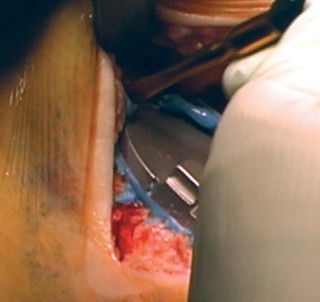

The most ubiquitous approach for TKA is the medial parapatellar arthrotomy. A straight, anterior longitudinal skin incision is made, extending from just proximal to the superior pole of the patella to just medial to the tibial tubercle. Full-thickness fasciocutaneous flaps are elevated to preserve the subdermal vascular plexus. The arthrotomy is then initiated through the medial retinaculum, coursing proximally into the quadriceps tendon (leaving a small medial cuff for later repair) and distally along the medial border of the patella and patellar tendon.

Once the joint is entered, the patella is either everted laterally or laterally subluxated, depending on the surgeon's preference and the stiffness of the extensor mechanism. A meticulous synovectomy and excision of the infrapatellar fat pad (Hoffa's fat pad) are performed to enhance visualization of the lateral compartment and the tibial plateau. All peripheral osteophytes on the femur and tibia must be aggressively resected at this stage. Retained osteophytes will artificially tension the collateral ligaments, leading to erroneous gap balancing and postoperative stiffness.